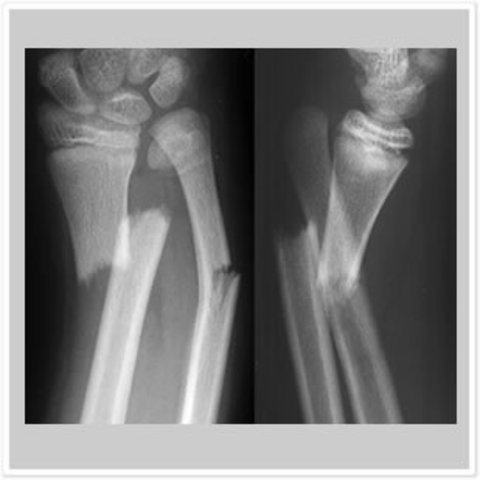

• Arm fracture

Arm fracture

Champions rise to the ocasion. When they get injured they redeem their selves by making a comeback greater than when I knocked somebody out. our society wants these great comebacks the King has performed. I decided to get out of my cast when I felt like I was ready to perform at the level I was at before my arm was fractured.